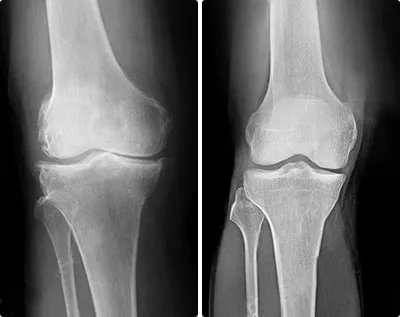

9.22% Sportivii sunt cei mai frecvenți clienți ai sălilor de recuperare fizică terapeutică și de fizioterapie. Ei prezintă leziuni cu diferite grade de severitate care pot fi împărțite în două grupuri: leziuni musculare și leziuni articulare. Rupturi, întinderi, artroză cronică. Nu poți evita riscurile dacă nu te protejezi la timp.